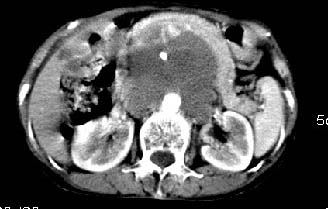

女:61岁.腹痛腹胀20天,行b超腹膜后实性占位.扫完后我查体发现患者右颈根部约3厘米类圆性包块,有移动{我考虑右颈根部包块是肿大淋巴结}.

ct:肝胃之间、胰头后、腹主a周围,融合而成团块状影,包绕血管,胰腺前移后缘分界欠清,与肝胃分界清,肿块未见明显强化,肝右叶后段小囊肿。

女:61岁.腹痛腹胀20天,行b超腹膜后实性占位.扫完后我查体发现患者右颈根部约3厘米类圆性包块,有移动{考虑右颈根部包块是肿大淋巴结}.

诊断:淋巴瘤>转移瘤。

肝胃之间、肝十二指肠韧带,胰头后、腹主a周围,融合而成团块状影,包绕血管[腹腔干、肠系膜上动脉,腹主动脉],胰腺前移后缘分界欠清,与肝胃分界清,肿块未见明显强化,肝右叶后段小囊肿。

考虑1淋巴瘤。2转移瘤。3恶性组织细胞瘤。

主动脉-胰腺间隙可见巨大分叶状软组织肿块影,包绕腹主动脉、腹腔干及其分支、腔静脉等大血管,增强呈无明显强化,临近脏器明显受压移位,增强示有分界。肝右叶可见局限性低密影,边缘清楚。

考虑腹膜后淋巴瘤。